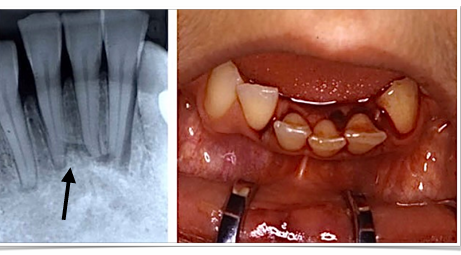

horizontal root fractures

-the more apical the fracture, the better the prognosis

-more apical means being more walled-off from the oral environment

-apical segment: blood supply maintained, never a problem

-coronal segment at risk: mobility, splint required for 4 weeks, RCT not needed (just observe)

-when coronal pulp necroses, see if you can reposition the segment and splint, or can do RCT on the coronal segment only

-if apical segment starts trouble, just do apicoectomy to treat